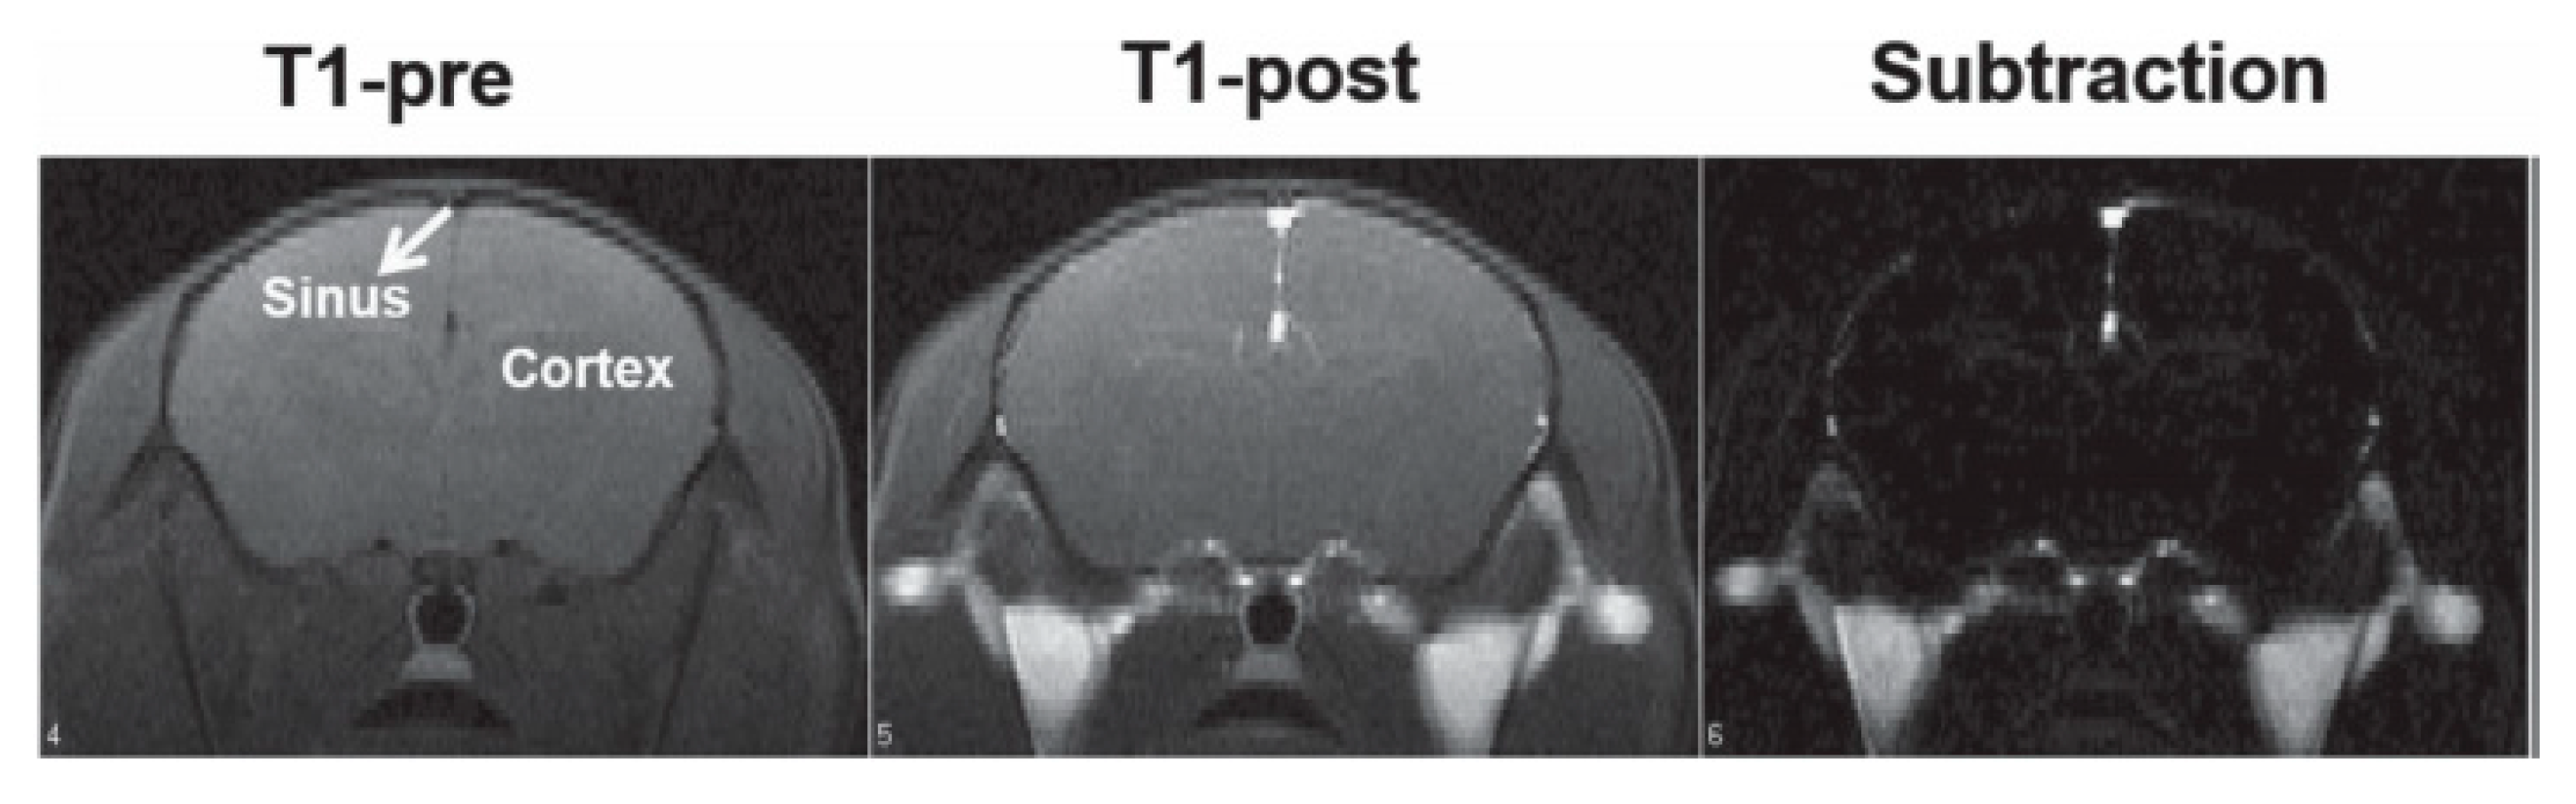

- Liu, C.-L.; Peng, Y.-K.; Chou, S.-W.; Tseng, W.-H.; Tseng, Y.-J.; Chen, H.-C.; Hsiao, J.-K.; Chou, P.-T. One-Step, Room-Temperature Synthesis of Glutathione-Capped Iron-Oxide Nanoparticles and their Application in In Vivo T1-Weighted Magnetic Resonance Imaging. Small 2014, 10, 3962–3969. [Google Scholar] [CrossRef]